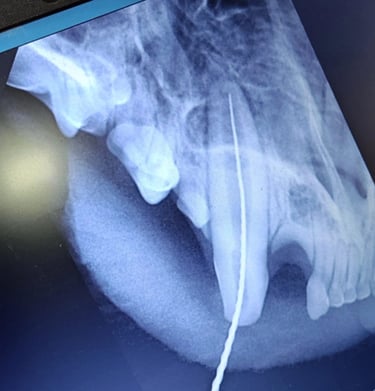

Exámenes Dentales

Revisiones completas con Radiografía Intraoral para garantizar la salud bucal de su mascota.